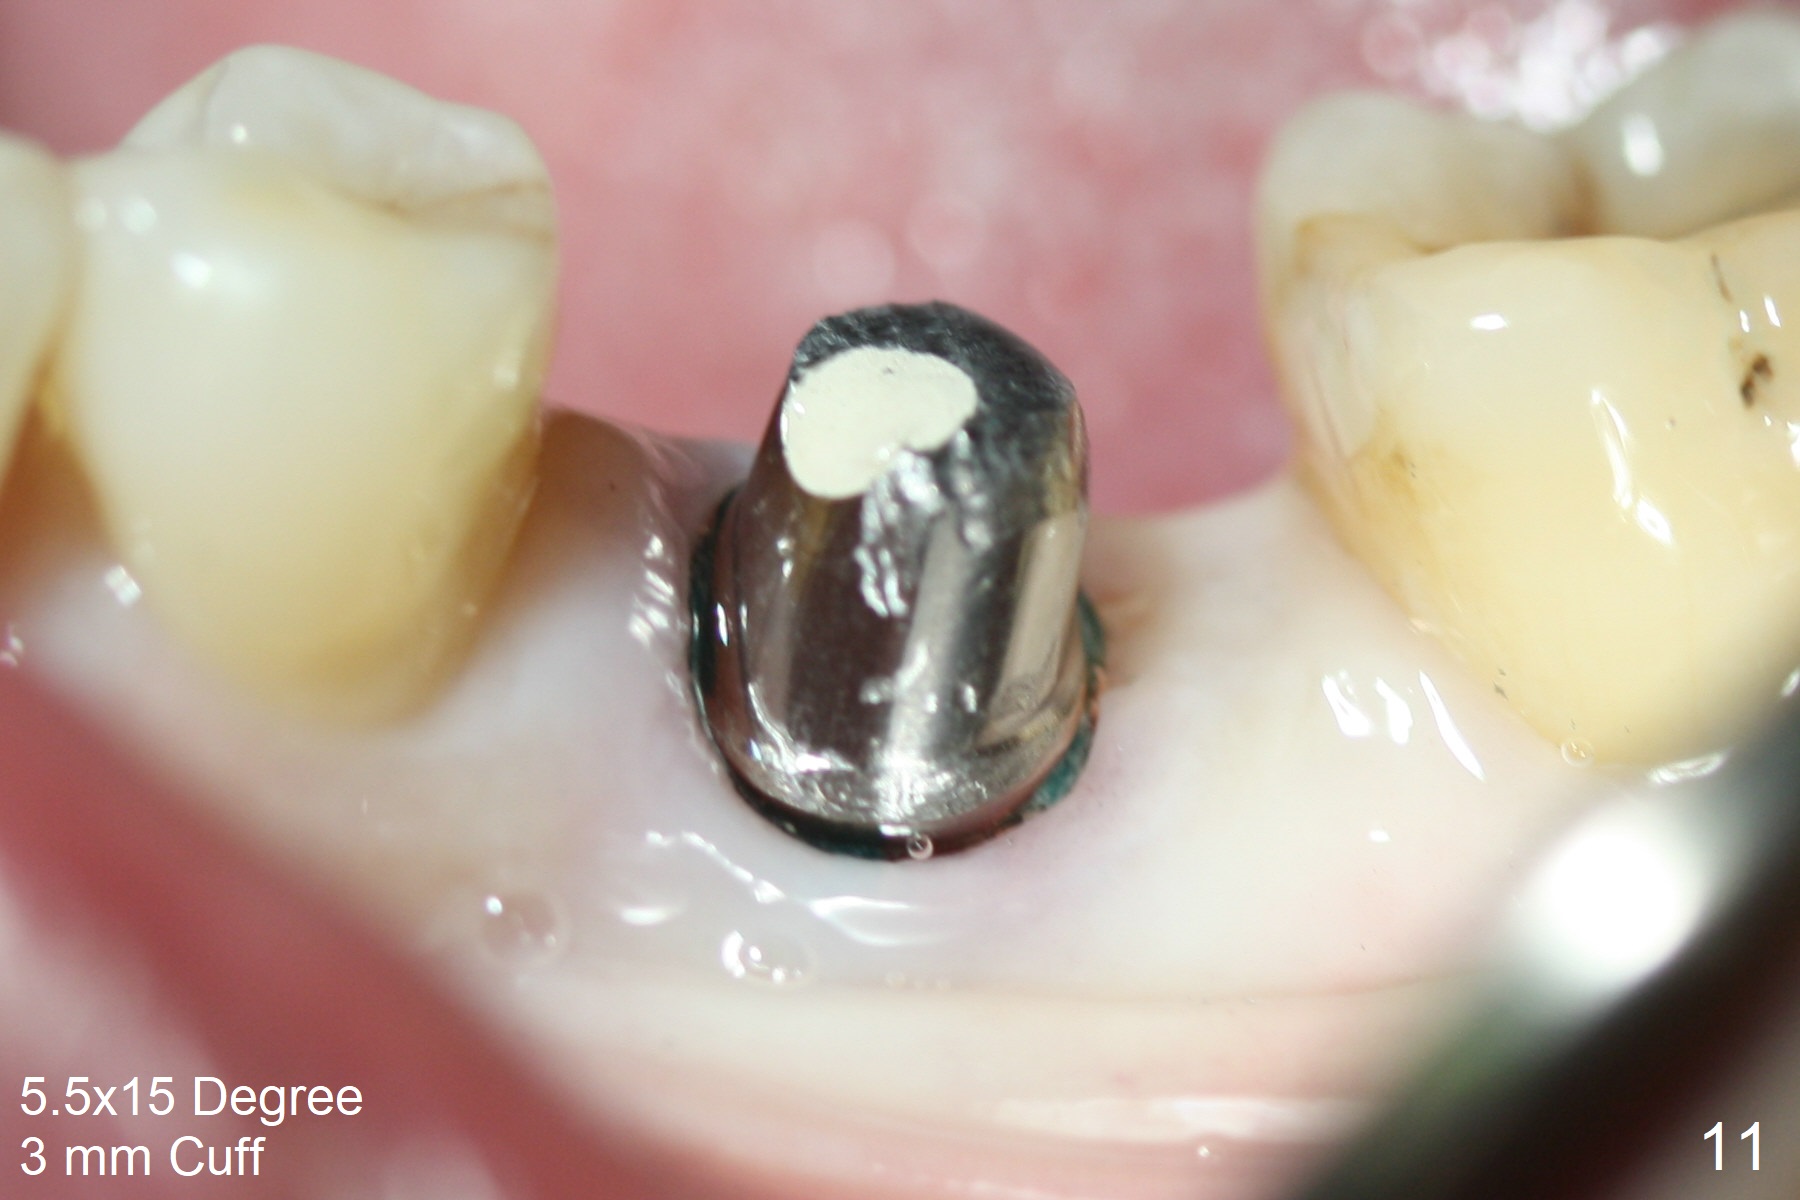

When the patient returns 9 months later, there is severe buccal gingival recession and abscess at #19 (Fig.1 *) with large mesial periradicular radiolucency (Fig.2 *).  The septum is thin and the buccal crest is low after extraction (Fig.3 * (mesial root vertical fracture)).  Osteotomy is initiated in the mesial socket immediately against the septum (Fig.4.5) with ~ 5 mm in the native bone.  Due to severe buccal plate resorption, a shorter implant is placed (Fig.6; 5x15 mm in stead of 18 mm).  There is at least 2 mm gap buccally for Vanilla Graft, which is also placed next to the implant and the neighboring root (Fig.7 *).  There is clearance from the Inferior Alveolar Canal (Fig.8 red dashed line).  Both the mesial and distal sockets heal 5.5 months postop (Fig.9), although the apical portion of the distal socket was not filled with allograft (Fig.7).  The implant was placed mesial.  The straight abutment (6.5x4(4) mm) (Fig.10) is changed to an angled one (5.5 x15 degrees 3 mm cuff (Fig.11)) before impression.  The implant is also placed buccally.  Therefore the implant position is far more important than its length.  The abutment is retightened 2.5 months post cementation, which is related to mesiobuccal placement of the implant (Fig.12).  An ideal trajectory is determined by drawing 2 horizontal lines (at crestal and apical levels: red lines in Fig.13), finding a central point of each line (vertical short line) and joining these 2 central points (Fig.14 pink line).  In fact the ideal osteotomy should have been established distal to the septum in this case.  Guided surgery may alleviate the issue.  The crown is not loose, but the patient feels that the implant tooth cannot sustain mastication.  In fact the screw is removed with hand driver (not wrench).  The abutment hex is rounded and worn.  A new 5.5x4(4) mm abutment is placed (without knowledge of previous use of an angled abutment) with mesial reduction to reduce undercut and buccodistal margin lowered to reduce gingival embrasure. It is that the straight abutment could decrease the chance of screw loosening.  Otherwise the implant has to be removed for better trajectory.